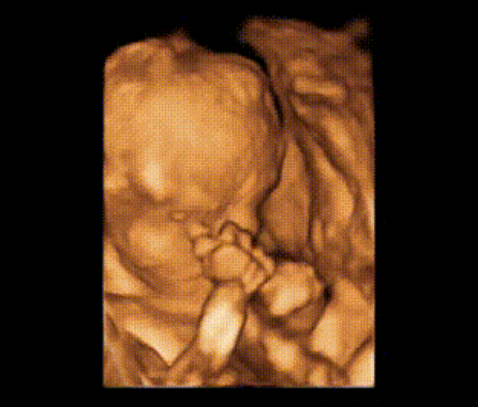

通过四维彩超成像和我隔空见面

四维彩超就是四维成像技术(4D),能直观、立体显示人体器官的三维结构及动态、实时地观察立体结构。四维彩超可以检查胎儿的发育情况,筛查先天疾病。如胎儿唇腭裂、四肢发育畸形、脑膜膨出、脊柱裂、腹壁裂等先天畸形。

这段时间正是大脑突飞猛进的发育时期,这个时期的胎儿结构已经形成,胎儿的大小以及羊水适中,在宫内的活动空间较大,胎儿骨骼回声影响比较小,图像也比较清晰,准妈妈千万不要错过咯。